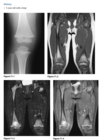

39 yo man fall

Axial T2 fat sat MR - bone contusions in medial patella and lateral femoral condyles (Arrows) with associated tear of medial retinaculum (Arrowhead)

Diagnosis: Acute patellar dislocation relocation

Occurs with internal rotation of femur on fixed and externally rotated femoral condyle - bone contusions on both.

Due to direct impaction, associated with ACL tears.

Radiographs = Lipohaemarthrosis or chip fracture adjacent to donor site of medial facet of patella.

MR findings = Disruption or sprain of the medial retinaculum, lateral patellar tilt or subluxation, lateral femoral condylar and medial patellar osseous contusions. Osteochondral injury to medial patella or lateral femur.